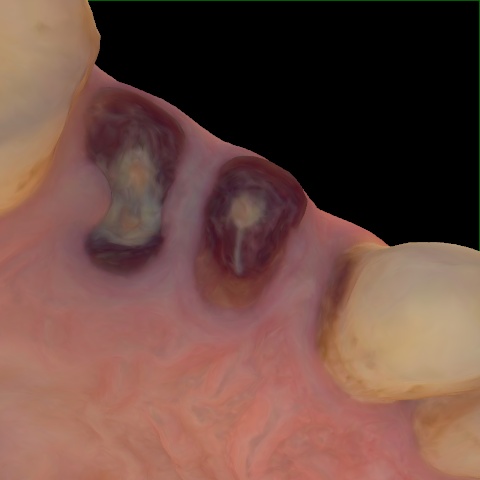

NHD36692

Annotated as "Good"